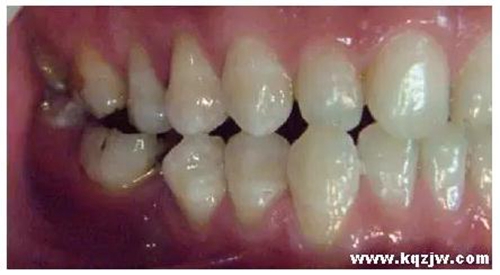

這種咬合接觸的結(jié)果是局部的咬合力集中在凸點(diǎn)接觸的位置,不能被有效分散,可造成受力部位牙體、牙周組織的應(yīng)力集中。最常見的表現(xiàn)是后牙頰舌向呈對刃關(guān)系,另外還常見于不完全遠(yuǎn)中關(guān)系或不完全近中關(guān)系的情況,此時(shí)從近遠(yuǎn)中方向來看,上下后牙牙尖之間凸凸相對(圖3)。

圖3 后牙凸凸接觸關(guān)系